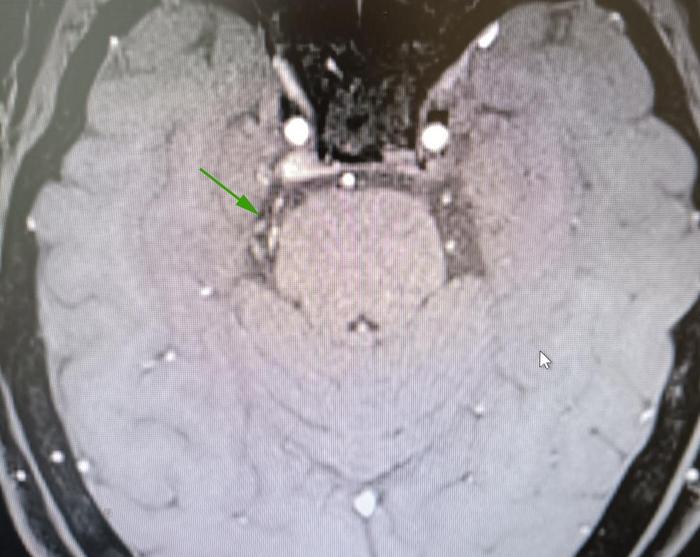

术前MRI显示:右侧三叉神经旁边有血管影

经过术前准备,于2022-7-8行右侧三叉神经显微血管减压术(MVD)

显露责任血管:小脑上动脉